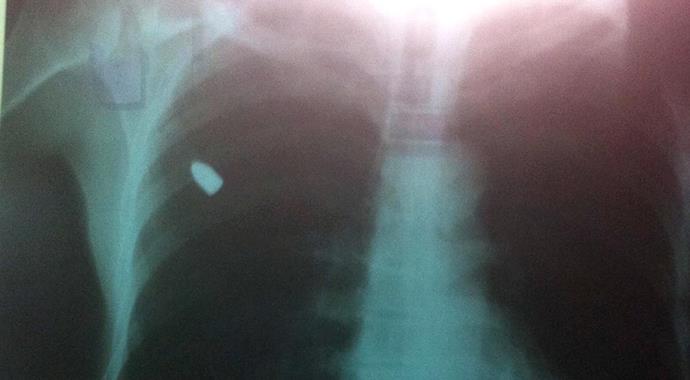

Derik İlçesi'ne bağlı Tepebağı Mahallesi'nde oturan Selahattin Dağlık dün gece evinin avlusunda uyurken göğsünde bir acı hissetti. Yakınları tarafından Derik Devlet Hastenesi'ne götürülen Dağlık, doktorun şikayetini sorması üzerine avluda uyuduğu sırada nereden atıldığı belli olmayan bir taşın göğsüne isabet ettiğini ve göğsünün kanadığını söyledi. Bunun üzerine muayene edilen röntgeni çekilen Dağlık'ın sağ göğsünden giren bir kurşunun akciğerine saplandığı anlaşıldı. Bunun üzerine Mardin Devlet Hastanesi'ne sevk edilen Selahattin Dağlık ameliyata alındı. Dağlık'ın göğsünden girip sırt kısmında kalan kurşun, başarılı bir operasyonla çıkarıldı.

Evde yatarken göğsüme bir cisim çarptığını ve acı ile uyandığını belirten Selahattin Dağlık şunları anlattı: "Kalktığım yerden çevreme göz gezdirdim. Çevrede bir şey görmedim. Evim İlçe Jandarma komutanlığına 150 metre mesafededir. Mermi oradan mı geldi bilmiyorum. Verilmiş sadakamız varmış. Mermi göğsümden girmiş ve sırtımda kalmış. Beni hemen Mardin Devlet Hastanesi'ne götürdüler. Ameliyatla o mermi çıkarıldı. Kim bunu bana yapmışsa ortaya çıksın. Ben o zaman davacı olmam. Eğer ortaya çıkmazlarsa davacı olacağım."